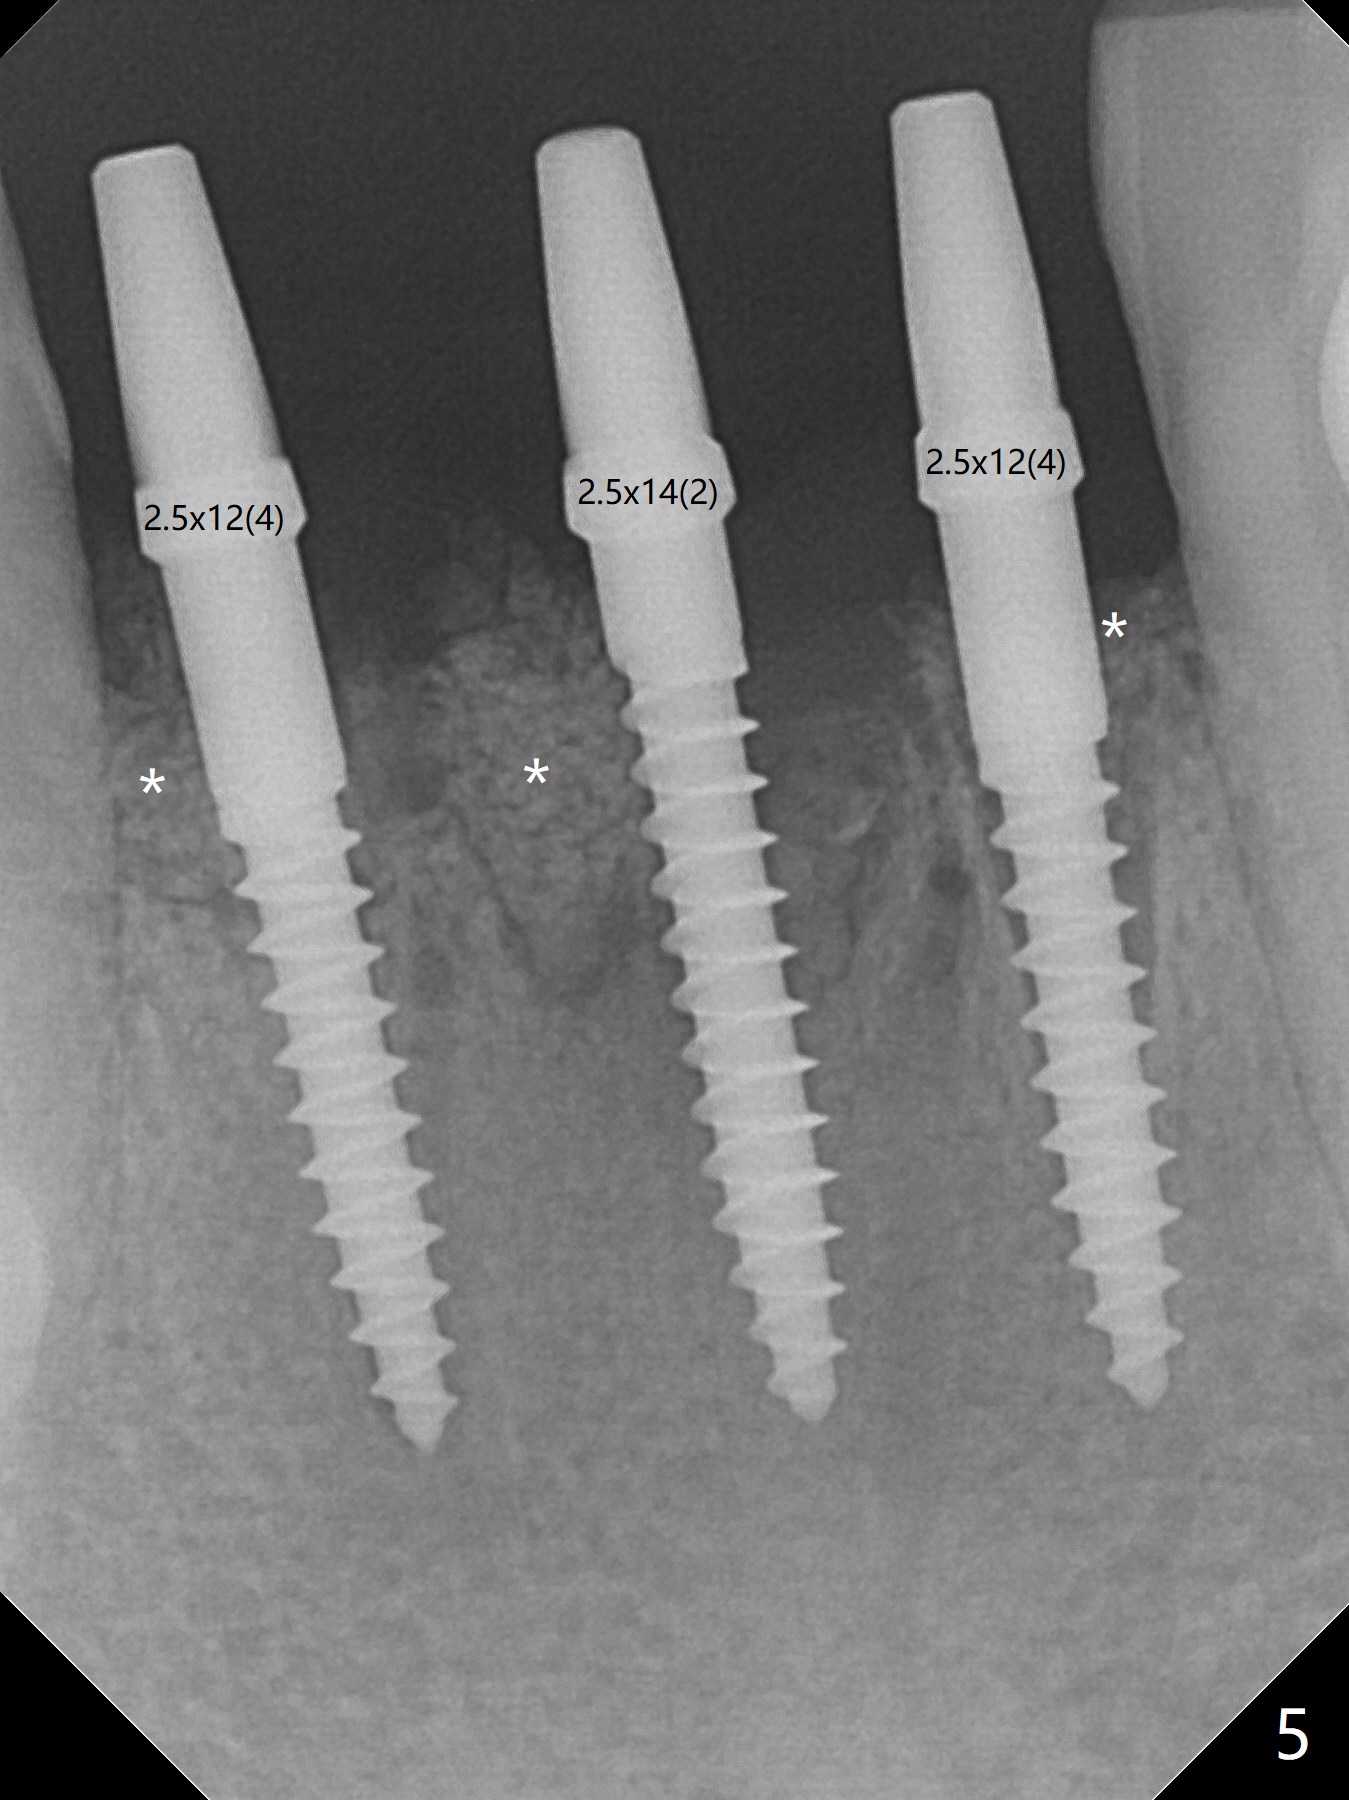

When the patient returns, the tooth #24 has exfoliated, while the ones at #25 and 26 has mobility III (Fig.1). The patient requests the tooth #23 extraction (Fig.2), but not #27. After SRP and extraction, osteotomy is initiated mesial to the sockets #23,25 and 26 (Fig.3,4) with intention to place 3 1-piece implants for 3 incisor crowns (Fig.5,6). Following Vanilla graft (Fig.5 *) a splinted provisional is fabricated to close the sockets (Fig.6). Peri-implant spaces close 5.5 months postop (Fig.7). Impression is taken after reprep for margin and parallelism (Fig.8). The final restoration consists of #23 single unit crown and #24-26 3-unit FPD (Fig.9). It appears that 2.5 mm 1-piece implants are not too small for the lower incisors (Fig.10-12), especially the central one (Fig.11). There may be perforation in the apical half of the lingual plate (L in Fig.10). The patient is not pleased with the shade of the #24-26 3-unit FPD (Fig.13 (6 months post cementation)). There is metal show through the abutments (*).